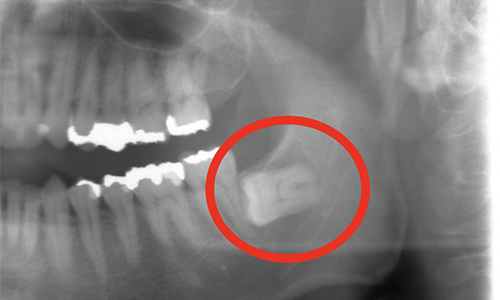

突然ですが皆さんは「親知らず」生えていますか??僕は3本はすでに抜歯していて、残り1本は残っている状態でした。 なぜ1本だけ残っているか・・・それは歯茎の中に完全に埋まっていて(しかも横向き)簡単には抜歯することができなかったからです。(既...